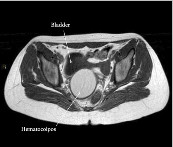

Pediatria per immagini

Una linfangite rapidamente "strisciante"

- Paiano R, Aimone Prina V, Nicolì S, Campisi Frascà G, Brandolisio LR, Feresin MG, Lorenzoni G, Bondone C, Manzoni P